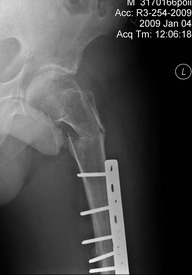

Больной 42 лет получил перелом проксимального отдела бедра. Ранее (1 год назад) оперирован на том же бедре по поводу оскольчатого диафизарного перелома. Четкой консолидации диафизарного перелома на рентгенограммах нет. Сопутствующие заболевания - tbs и гепатит С. При обсуждении хотелось бы услышать варианты лечения 1) "в идеале" и 2) с учетом социального статуса. Спасибо, А.Ситник

На снимке есть только дистальный отдел бедра, похоже, еще (или уже?) несросшийся на

фоне DCS. Что за перелом проксимального бедра, пока информации нет. Шлите снимки. И узнать бы, что доступно на месте для этого пациента.

Р-гр шейки